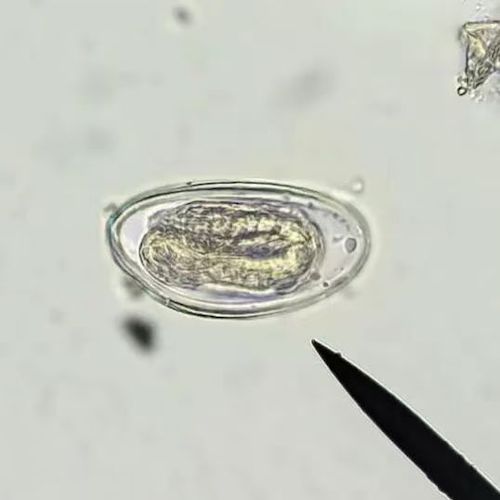

优秀作品展示

一等奖

第三组

王绍桁 李 帅 卢红宇 陆艺晨